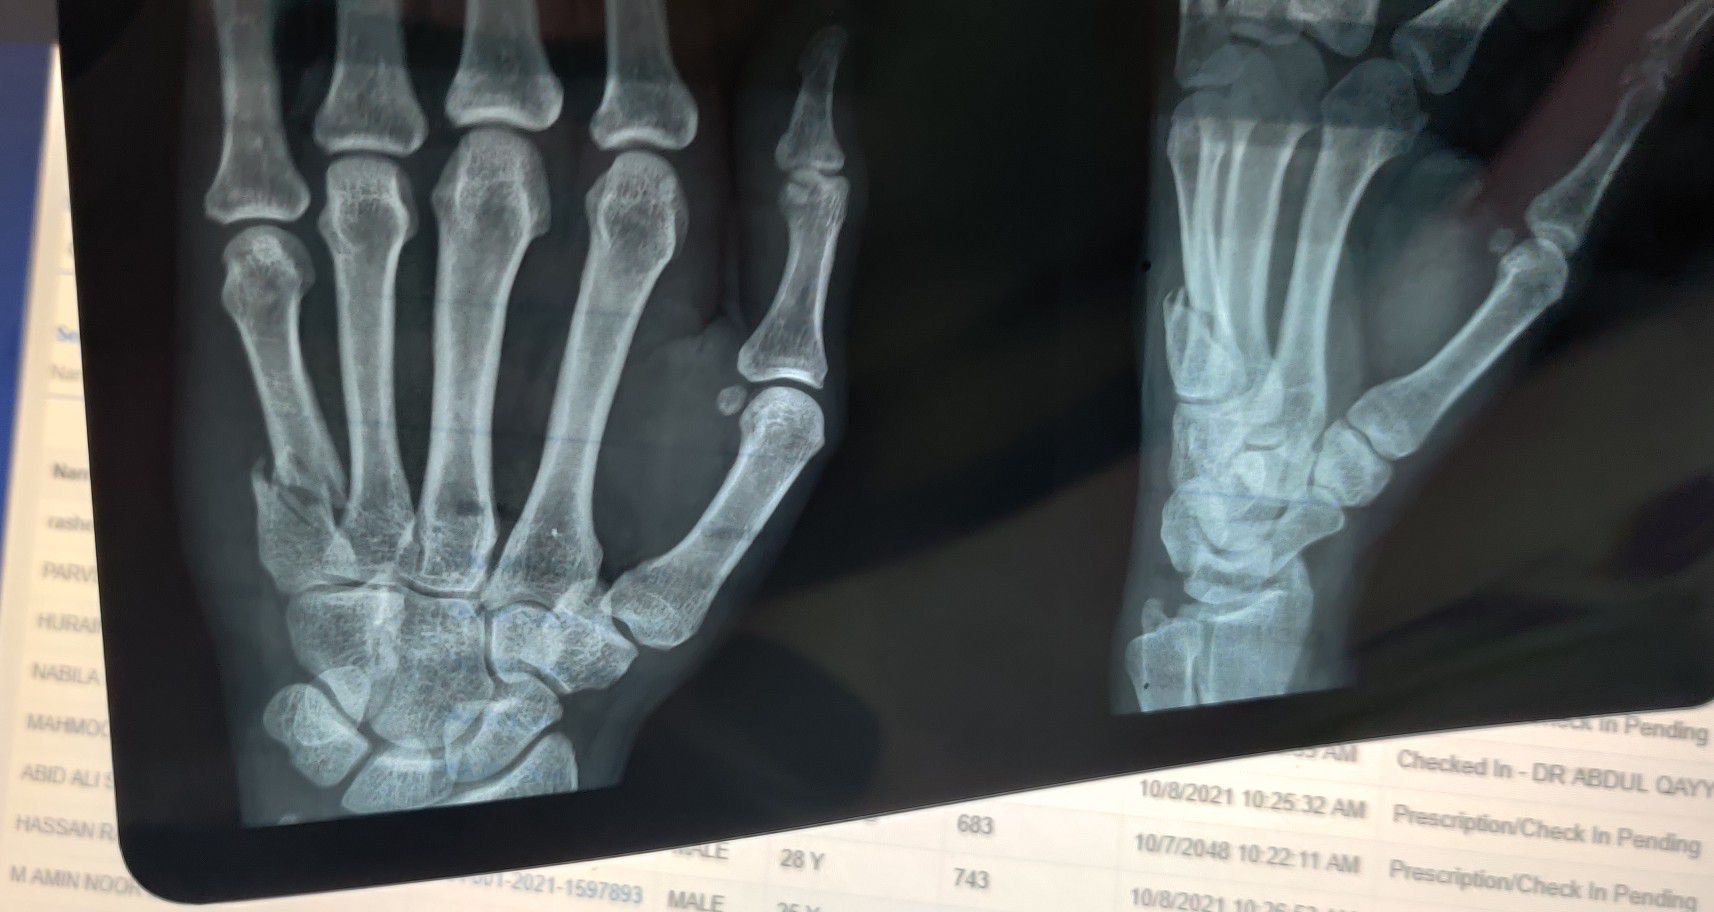

Fracture 5th MC Base

Xray

Hand

Metacarpal